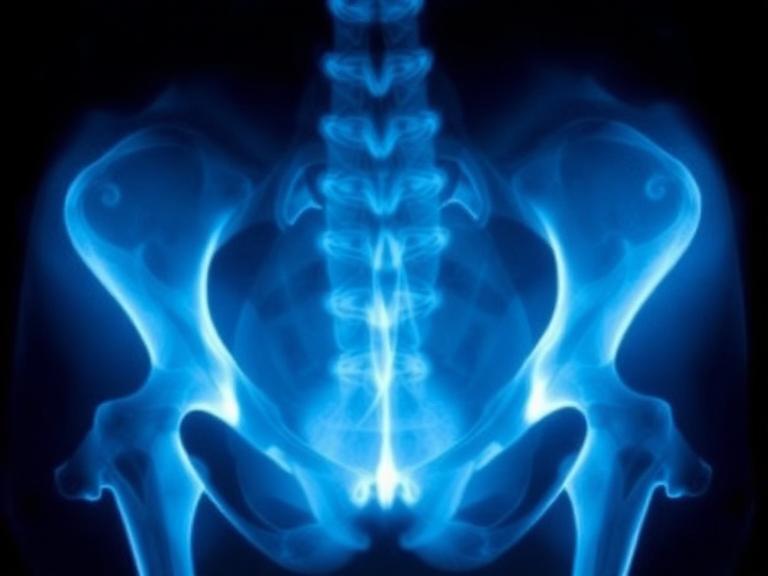

اشعة الحوض المنزلية هي خدمة طبية يتم من خلالها إجراء تصوير لمنطقة الحوض باستخدام أجهزة أشعة حديثة متنقلة، يقوم بها فريق متخصص داخل منزل المريض.

تشمل هذه الأشعة تصوير:

- عظام الحوض

- المفاصل

- الأنسجة المحيطة

- بعض الحالات المتعلقة بالجهاز البولي والتناسلي